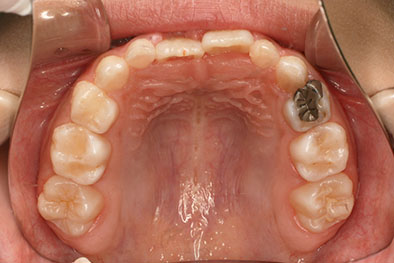

受け口を気にされ、他院からの紹介で来院された患者さんです。

小学2年生、生え変わりの時期から小児矯正を開始しました。

小児矯正で前歯の咬み合わせを改善し、

永久歯列完成後の中学生から非抜歯治療にて本格矯正を開始。

配列し仕上げました。